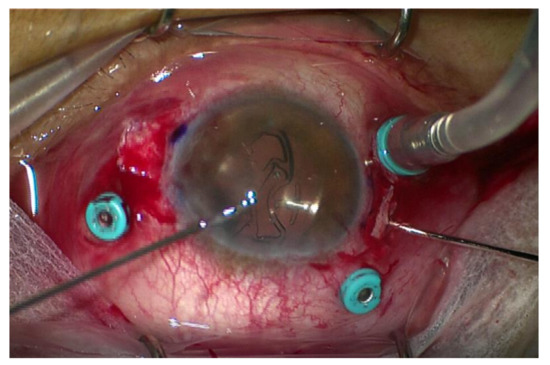

2.2.2. Sutureless Trans-Scleral Plugs Fixated Lens

2.3.2. Sutureless Trans-Scleral Plugs Fixated Lens Group (Group 2)